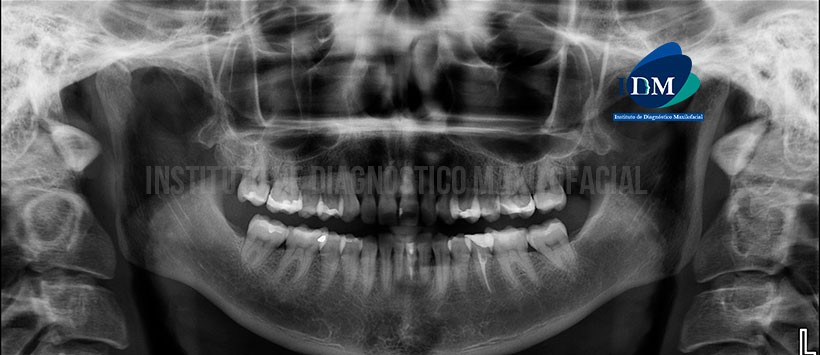

A la evaluación de la radiografía panorámica se evidencia neumatización alveolar de ambos senos maxilares, apiñamiento dentario del sector anterior, ausencia de terceras molares, múltiples restauración y material de obturación de conductos en la pieza 35 (Figura 1)